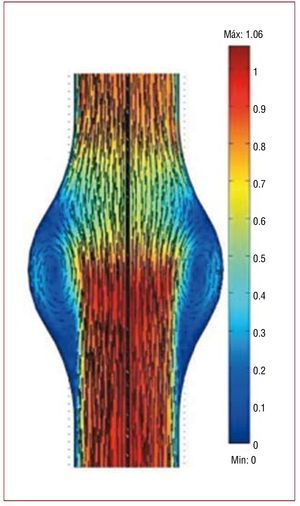

It appears reasonable to expect that the very same factors that lead to the formation of the aneurysm also determine the enlargement process. Thus, the flow-shear endothelium-mediated initiation hypothesis has motivated a great number of numerical and experimental fluid mechanics studies aimed at determining the characteristics of the flow shear stresses on the walls of AAA at different stages of their development. These studies have mainly consisted of experiments and numerical simulations using ideal symmetric and nonsymmetric shapes of fusiform aneurysms, and using realistic geometries reconstructed from the patient-specific 3D volume rendering of high-resolution CT scans and angiographies,97-103,105,108,109,113-121 among many others. Although all these numerical and experimental studies suffer from the inherited uncertainties which result from the difficulties involved in setting up the appropriate initial and boundary conditions, as well as accounting for the exact elastic properties of the wall discussed in the previous section, they have clearly shown that once a fusiform aneurysm forms, the flow is dominated by the onset of an unsteady, massive separation from the walls which occurs immediately after the peak systole (Figure 6). When the flow separates from the walls during the deceleration portion of the cardiac cycle, a large vortex forms in the cavity and the blood slowly recirculates in the cavity. Meanwhile regions of near stagnation are formed in the proximal and distal ends of the cavity (Figure 6).

Figure 6. Velocity field at peak systole inside an abdominal aortic aneurysm. The blood flow is from bottom to top. The velocity field is illustrated by the vector maps and has been normalized with the velocity at peak systolic in a healthy aorta. Note the formation of slowly recirculating regions (blue) with near stagnation in the proximal and distal sections of the cavity. Over time, these flow conditions lead to the formation of an intraluminal thrombus which eventually may occupy the whole bulge (blue region). Adapted from Tang et al.212